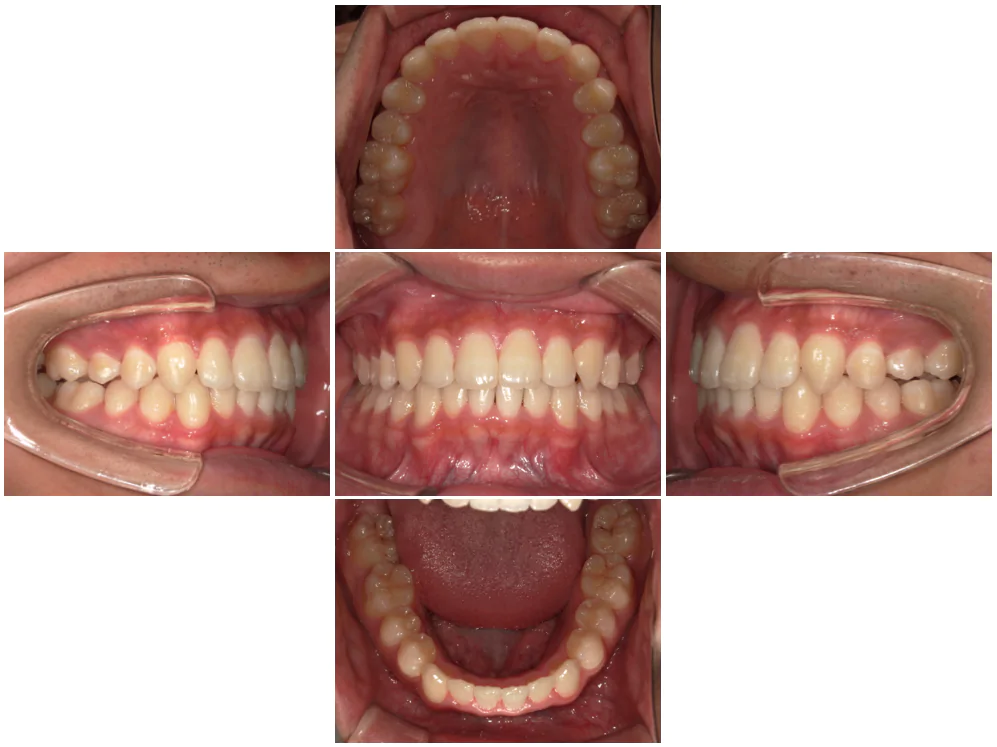

症例3

| 来院時の主訴 | 歯の間の隙間を閉じたい |

| 医院での対応や適用装置 | マウスピース矯正装置を使用して主訴である歯の間の隙間を閉じて改善を行いました。 歯の隙間の原因は飲み込み時に舌を前に出してしまう癖だと考えられましたので、 トレーニングを行い癖も無くなりました。 |

| 通院期間 | 6ヶ月 |

| 通院回数 | 5回 |

| 治療費用総額 | 577,500円(税込) |

| リスクと副作用 | 矯正治療による歯の移動に伴う痛み、歯根吸収、虫歯 |